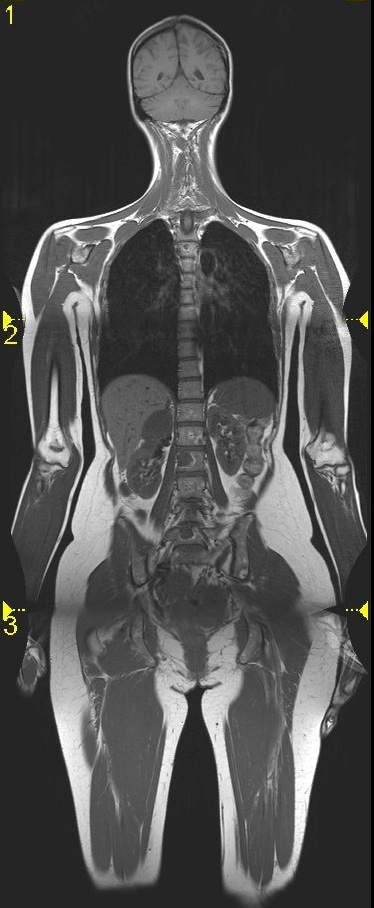

Damit belegt die MRT bei der Detektion von Knochenherden uneingeschränkt Platz eins, denn auch eine Szintigraphie zeigt einen Befund erst bei einer Reaktion des Knochens. Zudem gibt es Metastasen, die szintigraphisch okkult sind, insbesondere bei rein osteolytischen Herden. In der 2-Zentren-Studie von Ohlmann-Knafo aus dem Jahr 2009 („Diagnostischer Stellenwert der Ganzkörper-MRT und der Skelettszintigraphie in der ossären Metastasendetektion bei Mammakarzinompatientinnen“) konnte zudem nachgewiesen werden, dass bei einer Skelettszintigraphie falsch negative Ergebnisse in sehr viel stärkerem Maß als bei der MRT auftraten. „Die Sensitivität lag bei der Ganzkörper-MRT bei 90 Prozent, bei der Szintigraphie hingegen nur bei 40 Prozent und auch die Spezifität war mit 94 Prozent im MRT höher als mit 81 Prozent bei der Szintigraphie. Diese Zahlen lassen auch deshalb aufhorchen, weil die Szintigraphie bei Brustkrebs eigentlich als der Goldstandard für das Aufspüren von Knochenmetastasen angesehen wird“, resümiert die Münchner Oberärztin.

Am Universitätsklinikum München erhalten vor allem junge Patienten und solche mit einem unerklärlichen Anstieg der Tumormarker eine Ganzkörper-MRT. „Grundsätzlich ist die MRT das Verfahren der Wahl bei Knochenmetastasen. Wenn ein Patient Wirbelsäulenschmerzen hat und die Anamnese einen Tumor ergeben hat, beginnt die Diagnostik primär mit dem Röntgen, meistens allerdings ohne Erfolg. Dann wird eine lokale MRT gemacht und wenn sich der Verdacht auf Metastasen bestätigt, schließt sich die Ganzkörperbildgebung für das Staging an. Dazu gehörten auch eine CT des Thorax und des Abdomens, um Herde in Lunge und Leber detektieren zu können“, schildert die Professorin.

Mit ihrer jüngsten Studie bestätigt Baur-Melnyk diese Vorgehensweise. In den vergangenen drei Jahren untersuchte sie 40 primär asymptomatische Brustkrebspatientinnen im Rahmen der PONS-Studie, einer patientenorientierten Nachsorgestudie. Normalerweise beschränkt sich die Brustkrebsnachsorge auf die Brust, andere Körperareale werden diagnostisch nicht abgeklärt. In dieser Studie wurden die Patientinnen, bei denen im Labor ein Anstieg der Tumormarker festgestellt wurde, zusätzlich im Ganzkörper-MRT untersucht. „Bei einem erheblichen Prozentsatz dieser Patientinnen konnten wir dabei Metastasen nachweisen, die sonst vermutlich primär unerkannt geblieben wären. Die Ganzkörper-MRT ist bezüglich der Detektion von Knochenherden und Organmetastasierungen besser als die PET-CT. Die PET-CT hingegen ist bei lokalen Rezidiven, bei Lymphknotenbefall und auch bei Lungenrundherden besser“, so Baur-Melnyk.